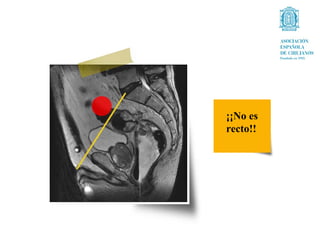

¡¡No es

recto!!